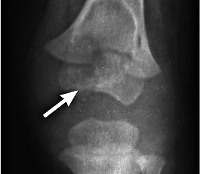

Туберкулиновые пробы подтверждают инфицированность пациента, но не являются основанием для постановки диагноза туберкулез суставов. Основным инструментальным методом диагностики становится рентгенография. Для более точной оценки стадии и выраженности процесса назначают сравнительные снимки здорового и больного суставов. В начальной стадии выявляется слабо заметный распространенный остеопороз. При малой форме остеопороз усиливается, при выраженной форме становится явным, хорошо заметным. При свежем абсцессе меняются только контуры окружающих мягких тканей, в последующем тень абсцесса становится крапчатой, а затем полностью обызвествляется. Для детального изучения костей и мягких тканей используют КТ сустава.